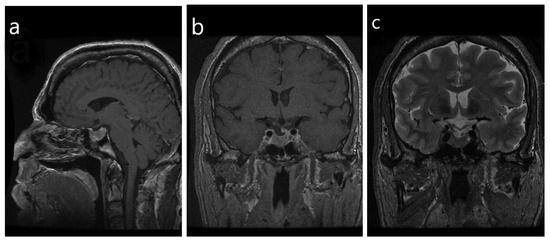

- Heck, A.; Ringstad, G.; Fougner, S.L.; Casar-Borota, O.; Nome, T.; Ramm-Pettersen, J.; Bollerslev, J. Intensity of pituitary adenoma on T2-weighted magnetic resonance imaging predicts the response to octreotide treatment in newly diagnosed acromegaly. Clin. Endocrinol. 2012, 77, 72–78. [Google Scholar] [CrossRef]

- Heck, A.; Emblem, K.E.; Casar-Borota, O.; Bollerslev, J.; Ringstad, G. Quantitative analyses of T2-weighted MRI as a potential marker for response to somatostatin analogs in newly diagnosed acromegaly. Endocrine 2016, 52, 333–343. [Google Scholar] [CrossRef] [PubMed]

- Potorac, I.; Petrossians, P.; Daly, A.F.; Alexopoulou, O.; Borot, S.; Sahnoun-Fathallah, M.; Castinetti, F.; Devuyst, F.; Jaffrain-Rea, M.L.; Briet, C.; et al. T2-weighted MRI signal predicts hormone and tumor responses to somatostatin analogs in acromegaly. Endocr. Relat. Cancer 2016, 23, 871–881. [Google Scholar] [CrossRef] [PubMed]